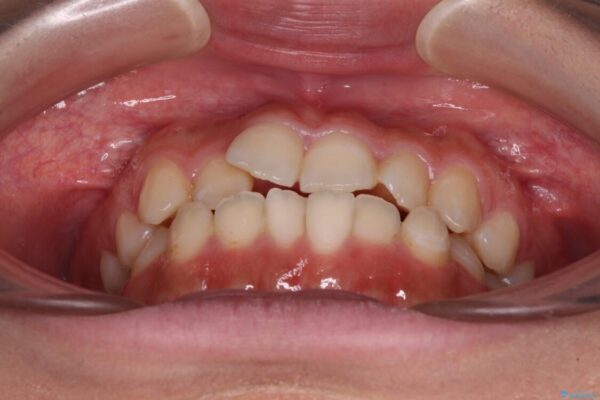

治療前

• 【モニター】短期間で終わりたい ワイヤー装置での非抜歯矯正 治療前画像

前歯のデコボコを気にして来院された患者様です。